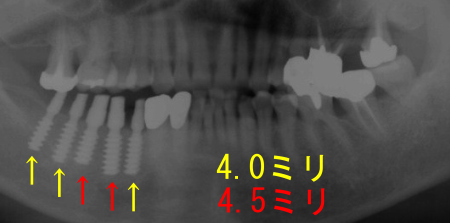

4.0ミリ、4.5ミリ、5.0ミリのインプラントの症例

下記は右から5.0ミリ、4.5ミリ

4.0ミリのインプラントです。